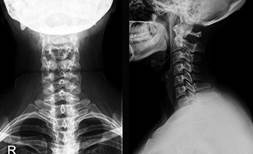

Как называется прибор, изображённый на фотографии, с помощью которого получили данное изображение?

прибор - полученное изображение

1) рентген-аппарат

2) спирометр

3) электрокардиограф

4) фонендоскоп

Ответ:

1

Что исследуют с помощью прибора, изображённого на рисунке?

1) артериальное давление

2) целостность костей

3) состав желудочного сока

4) состояние внутренних органов

4

Что исследуют с помощью прибора, изображённого на фотографии?